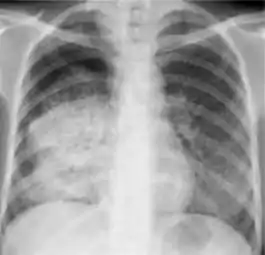

3. Discrete fibrotic scar with volume loss or retraction—Discrete linear densities with reduction in the space occupied by the upper lobe. Associated signs include upward deviation of the fissure or hilum on the corresponding side with asymmetry of the volumes of the two thoracic cavities.

Chest x-ray showing distinct fibrotic scar with volume loss or retraction with an upward deviation of the fissure or hilum on the corresponding side with asymmetry of the volumes of the two thoracic cavities.